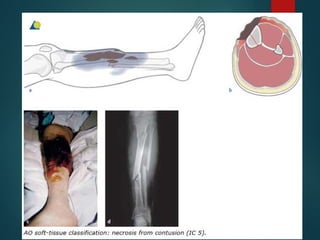

Closed skin lesions (IC)

IC5 Necrosis from contusion

Closed skin lesions(IC) IC 1 No skin lesion IC 2 No skin laceration, but contusion IC 3 Circumscribed degloving IC 4 Extensive, closed degloving IC5 Necrosis from contusion